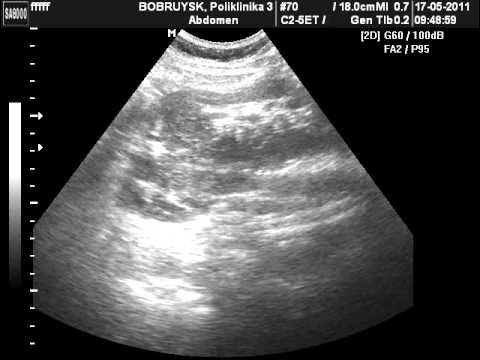

Анатомические особенности: L-образная и галетообразная почки